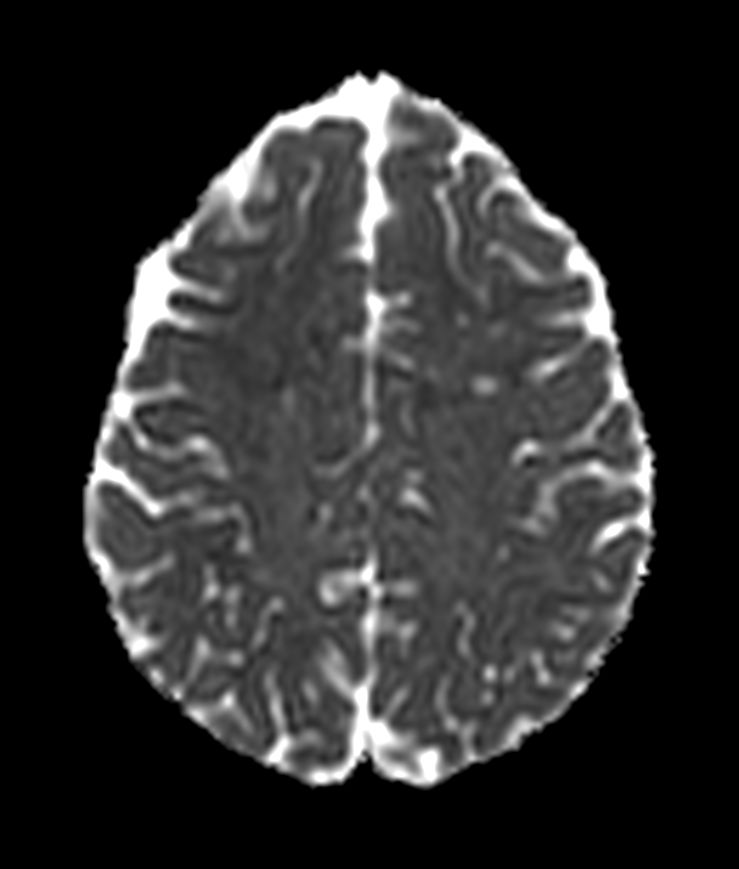

SWI sequence has a high sensitivity to enhance contrast for deoxygenated (venous) blood or calcium deposits. This may help, when used in combination with other clinical information, in the diagnosis of various neurological pathologies. 3D imaging lets you acquire high resolution data in multiple directions in one scan. Isotropic voxel size enables reformats in any plane without loss of resolution. FLAIR* requires offline post processing combining the contrast of 3D FLAIR and 3D SWI EPI into a single image. This enables the visualization of Central Vein Sign, mapping subcortical veins onto 3D FLAIR contrast images.